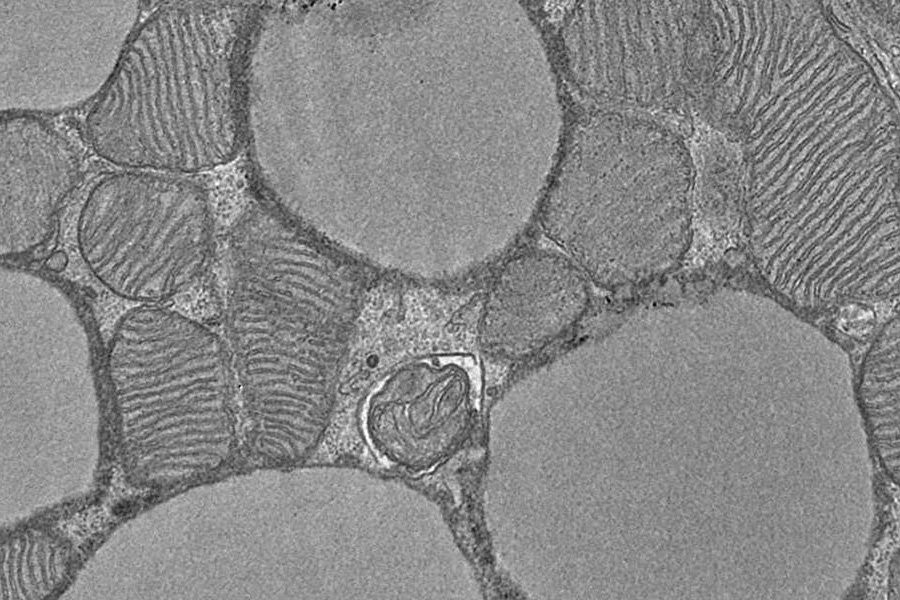

Клетки бурого жира особенно богаты митохондриями, энергетическими станциями , где происходит клеточное дыхание . Однако наука пока недостаточно понимает, как клетки бурого жира усиливают метаболизм, чтобы можно было разработать новые методы лечения.